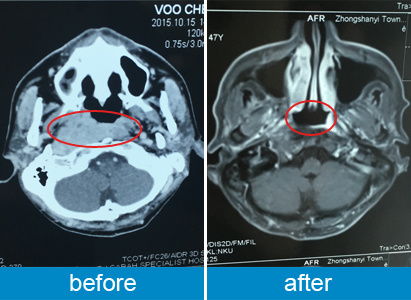

治疗前后CT对比图

入院时,邬秋华的肿瘤已经由第三期发展至第四期了,根据他的病情,医学肿瘤中心的MTD多学科治疗团队为他量身制定了以介治疗为主的治疗方案。介入治疗是在DSA造影设备下进行,开一个1-2毫米的切口,然后将特制的导管、导丝等精密器械引入到肿瘤部位,将抗肿瘤药物灌注到肿瘤内,以及对肿瘤本身和其供血动脉进行栓塞, 把供应肿瘤的血管“栓死”,使肿瘤失去血供从而“饿死”,同时栓塞剂可携带抗癌化疗药物进入肿瘤内,起到缓释和局部化疗作用。介入疗法具有痛苦少、疗效高、毒副作用小的特点。邬秋华表示,第一次接受介入治疗时,他并不紧张,且很轻松,他对治疗充满信心。事实证明,广州现代医院并没有让邬秋华失望,第一次介入治疗后,邬秋华的肿瘤已经由原来的4cm缩小至不到1cm。除了胃口稍差,邬秋华并没有出现其他放化疗常见的副作用,如呕吐、疼痛、脱发等。邬秋华表示,整个治疗比他预想的要轻松很多,他很喜欢介入治疗,既有效又少副作用。如今,邬秋华的肿瘤已经完全消失,生活也逐渐恢复正常。